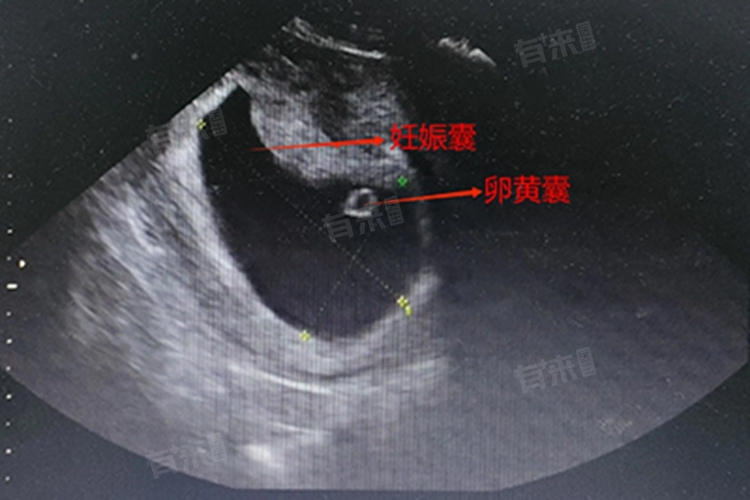

卵黄囊达到1.5-2.0cm时可见胎心、胎芽。在孕早期的胚胎发育过程中,卵黄囊的大小与胎心胎芽的出现有着密切的关系。通常情况下,当卵黄囊的直径达到1.5-2.0厘米时,通过B超检查便可以观察到胎心和胎芽。但是这一标准并非绝对,因为胎心胎芽的出现还受到多种因素的影响,包括孕妇的个体差异、胚胎的发育速度、月经周期的规律性以及营养摄入等。

- 卵黄囊是胚胎发育早期的一个重要结构,储存着营养物质,并具有分解、吸收和运输的功能。在胚胎发育的初期,卵黄囊为胚胎提供必要的营养支持,确保其正常发育。随着胚胎的不断成长,卵黄囊的大小也会逐渐增大。当卵黄囊发育到一定阶段,其内部的营养物质开始被胚胎吸收利用,同时胚胎的心脏也开始发育。

- 胎心是胎儿心脏发育的结果,而胎芽则是胚胎早期形态的一个阶段,包括了胎儿身体的初步结构和器官。在胎心胎芽出现之前,胚胎主要进行细胞分裂和形态分化,为后续的器官发育奠定基础。当卵黄囊达到一定大小时,胚胎的心脏开始形成并产生跳动,同时胎芽也逐渐形成并分化出各个器官。

- 卵黄囊达到1.5-2.0厘米时可见胎心胎芽,主要是因为在这个阶段,胚胎已经完成了早期的细胞分裂和形态分化,进入了器官发育的关键时期。此时,卵黄囊为胚胎提供了充足的营养支持,使得胚胎能够正常发育并出现胎心胎芽。